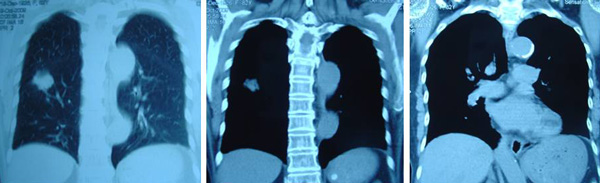

SH said she was well all these years and her progress was monitored by her doctor. About 10 years later, in early 2009, SH developed shortness of breath. She could not lift her left arm. She was tired and lost her appetite. A chest X-ray indicated large left pleural effusion. SH had the fluid in her lung tapped out. A CT scan on 7 January 2009 indicated several subcentimeter nodules in her left lung. The lymph nodes in the left axilla and aortopulmonary window were enlarged. Impression: left pulmonary and pleural metastasis.

SH sought a second opinion from another oncologist at a university hospital. Another CT scan was performed and it also confirmed a metastatic breast cancer with left pleural effusion with small benign liver cysts.

In August 2011 SH developed shortness of breath again. A CT scan on 4 August 2011 confirmed presence of mild left pleural effusion. Fluid was tapped out of her lung again.